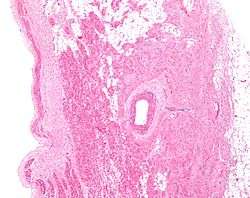

![]() Low magnification micrograph of a sinoatrial node (center-right on image) and its surrounding tissue. The SA node surrounds the (sinuatrial) nodal artery (on lumen in the image), a branch of the right coronary artery, abuts cardiac myocytes (of the right atrium) on its deep aspect (left of image) and adipose tissue on its superficial (epicardial) aspect (right of image). H&E stain. | |

The sinoatrial node is composed of a group of specialised cells positioned in the wall of the right atrium just lateral to the sinus venarum at the junction where the superior vena cava enters the right atrium.[1] The SA node is located in the myocardium just internally to the epicardium. Its deep aspect abuts cardiac myocytes belonging to the right atrium, while its superficial aspect is covered by adipose tissue. It is an elongated structure that extends between 1 and 2 cm on the right from the crista terminalis the crest of the right atrial appendage, and runs posteroinferiorly into the upper part of the terminal groove. SA node fibres are specialized cardiomyocytes that vaguely resemble normal, contractile cardiac myocytes; however, although they possess some contractile filaments they do not contract as robustly. Additionally, SA node fibers are measurably thinner, more tortuous and stain less intensely than cardiac myocytes.